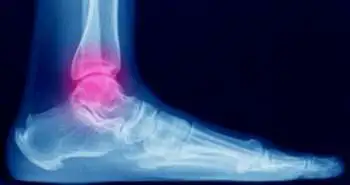

Trans fibular total ankle replacement shows remarkable improvements were observed in the range of motion, radiographic parameters and patient-reported outcomes for managing ankle arthritis, as per research published in Foot & Ankle International Journal. Ankle arthritis is a significant cause of disability and pain following degeneration of the quality of life. Prosthetic replacement of the ankle has shown to be a reliable choice with new advancements in surgical instrumentation and techniques as compared to arthrodesis with similar outcomes. This study aimed to assess the radiological and clinical outcomes of trans fibular total ankle replacement with two years follow-up.

A total of 89 patients with 53.2 ± 13.5 years mean age went through the trans fibular total ankle arthroplasty between May 2013 and February 2016. All patients were observed for two years after the treatment with a mean follow-up of  42.0 ± 23.5 months. Radiographic and clinical assessment of patients was done at six months, one and two years after the procedure.

A statistically significant improvement in the visual analog scale (VAS), Short Form-12 Physical and Mental Composite Scores, and American Orthopaedic Foot & Ankle Society (AOFAS) Ankle-Hind foot Score was seen after two years of follow-up  (P < .001). The ankle plantar flexion and dorsiflexion improved from 9.6 ± 5.8 and 6.2 ± 5.5 to 18.1 ± 7.6 and 24.2 ± 7.9, respectively. Management of neutral alignment of the ankle was also demonstrated at two years. No radiographic evidence of talar or tibial lucency was seen after the follow-up. Seven patients went through the operation again for symptomatic hardware removal; two patients noticed delayed wound healing. First patients operated with plate removal and flap coverage; whereas the second patient went for fibular plate removal. Postoperative prosthetic infection was seen in one patient who required operative debridement, placement of an antibiotic spacer, and removal of implants. Additional investigation is needed to discover the mid- and long-term performance of these implants.